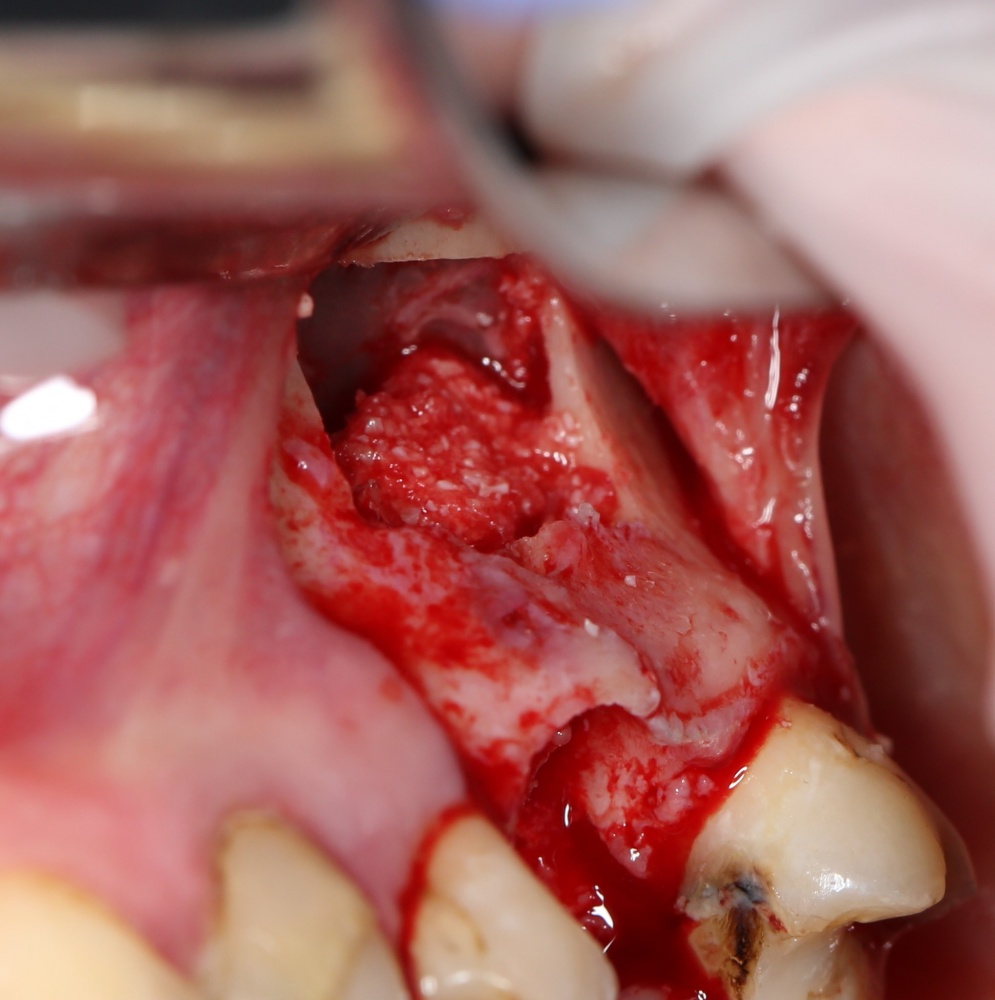

Возвращаемся к основной операционной области. Еще раз посмотрим на альвеолярный гребень, поофигеваем от его ширины и моих грандиозных планов:

Если ты читал мои предыдущие публикации, посвященные остеопластике, то наверняка знаешь, что костное ложе перед фиксацией графта (любого графта) требует некоторой подготовки. В основном она заключается в полном или частичном удалении кортикального слоя и, применительно к АТККФ — адаптации не только блока под ложе, но и ложа под пересаживаемый костный блок. Подробности здесь>>

Ежу понятно, что к необходимости этих манипуляций мы пришли не сразу. А тогда был 2013 год… и у меня были мысли, что подготовка костного ложа нужна не всегда и не всем. Здесь я понадеялся на размер костного дефекта и большую площадь контакта между костным аутотрансплантатом и принимающим ложем. Конечно, сейчас я сделал бы немного по-другому.

Я зафиксировал костный блок практически без адаптации на несколько винтов. Обрати внимание, что винты находятся в зоне, где не планируется установка имплантатов. Фиксация должна быть надежной, поскольку мне еще предстояла подготовка лунок для имплантатов. Трех винтов для этого вполне достаточно.